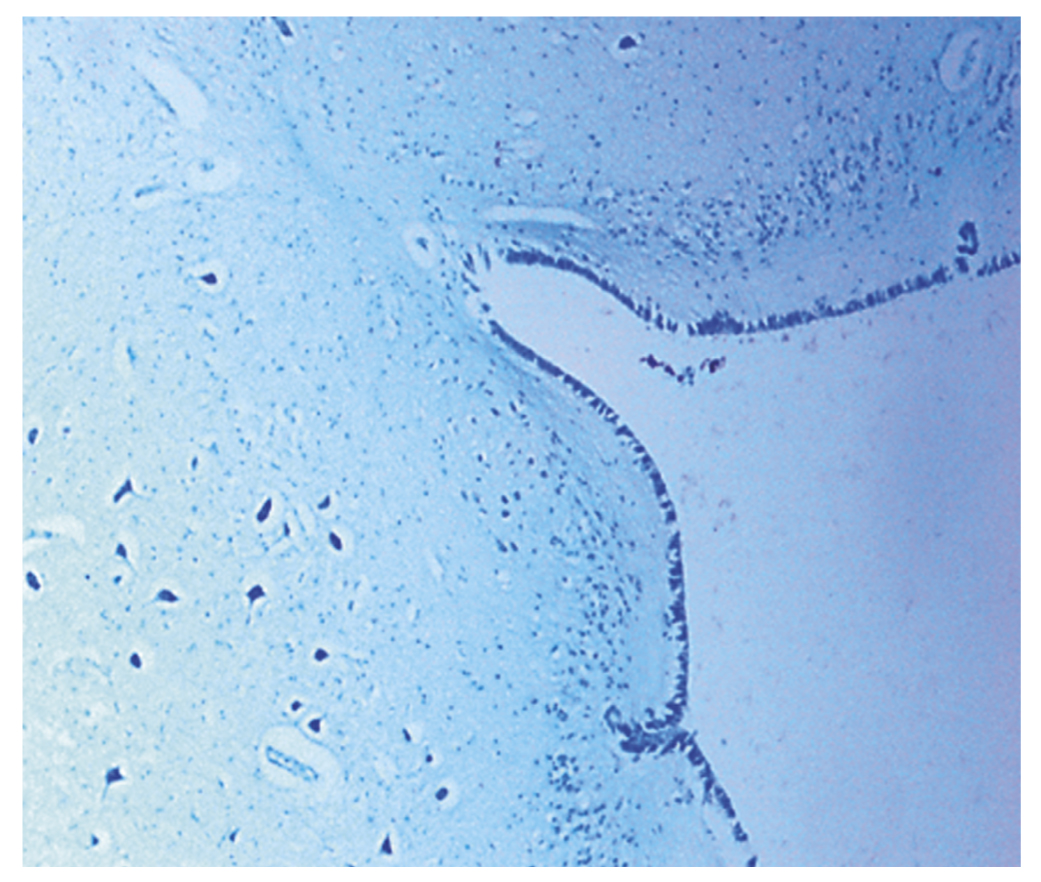

Вскрытия детей проводили в соответствии с медицинскими технологиями, применяемыми при производстве судебно-медицинских экспертиз [8]. Детальному макроскопическому изучению был подвергнут ствол мозга с учетом особенностей анатомического строения продолговатого мозга и локализации ядер черепно-мозговых нервов в дне ромбовидной ямки (рис. 1–4). При гистологическом исследовании кусочки внутренних органов и головного мозга подвергали стандартной парафиновой обработке, окрашивали гематоксилин-эозином и пикрофуксином по Ван Гизону в 100% случаев. Кусочки стволовых отделов мозга были дополнительно окрашены гистохимическими методами: по Вейгерту — на эластические волокна, по Шпильмейеру — на миелиновые волокна, толуидиновым синим по Нисслю — для изучения структуры нервной ткани. Общий объем изученных гистологических препаратов составил 12 321 срезов, которые изучали при помощи светового микроскопа «Olympus-CX 31» с микрофотографированием. Микроморфометрия производилась с использованием программного обеспечения Image J2x, что позволило определить площадь объекта, выделенного на фотографии гистологического препарата. При изучении микроскопических срезов продолговатого мозга в основной группе (СВСД) и группе контроля провели статистический анализ морфометрических измерений с помощью пакета статистических и прикладных программ Statistica 6.0 (США).

Рис. 3. Срединная борозда продолговатого мозга в микропрепарате (мальчик, 3 месяца 12 дней). Окраска толуидиновым синим по Нисслю. Ув. 40

Детальному исследованию и анализу был подвергнут ствол мозга с учетом особенностей анатомического строения продолговатого мозга и локализации ядер черепно-мозговых нервов в дне ромбовидной ямки (см. рис. 3 и 4). В 54 случаях (72,9%) при гистохимической окраске срезов толуидиновым синим по Нисслю в заднем (вегетативном) ядре блуждающего нерва, расположенном в проекции вагусного треугольника ромбовидной ямки, обнаружены явления хроматолиза, кариолизиса и нейронофагии [11]. Морфометрические показатели в нейронах и сосудах ствола мозга были статистически значимы между показаниями контрольной и опытной группы в сопоставимых возрастах (р ≤ 0,01).